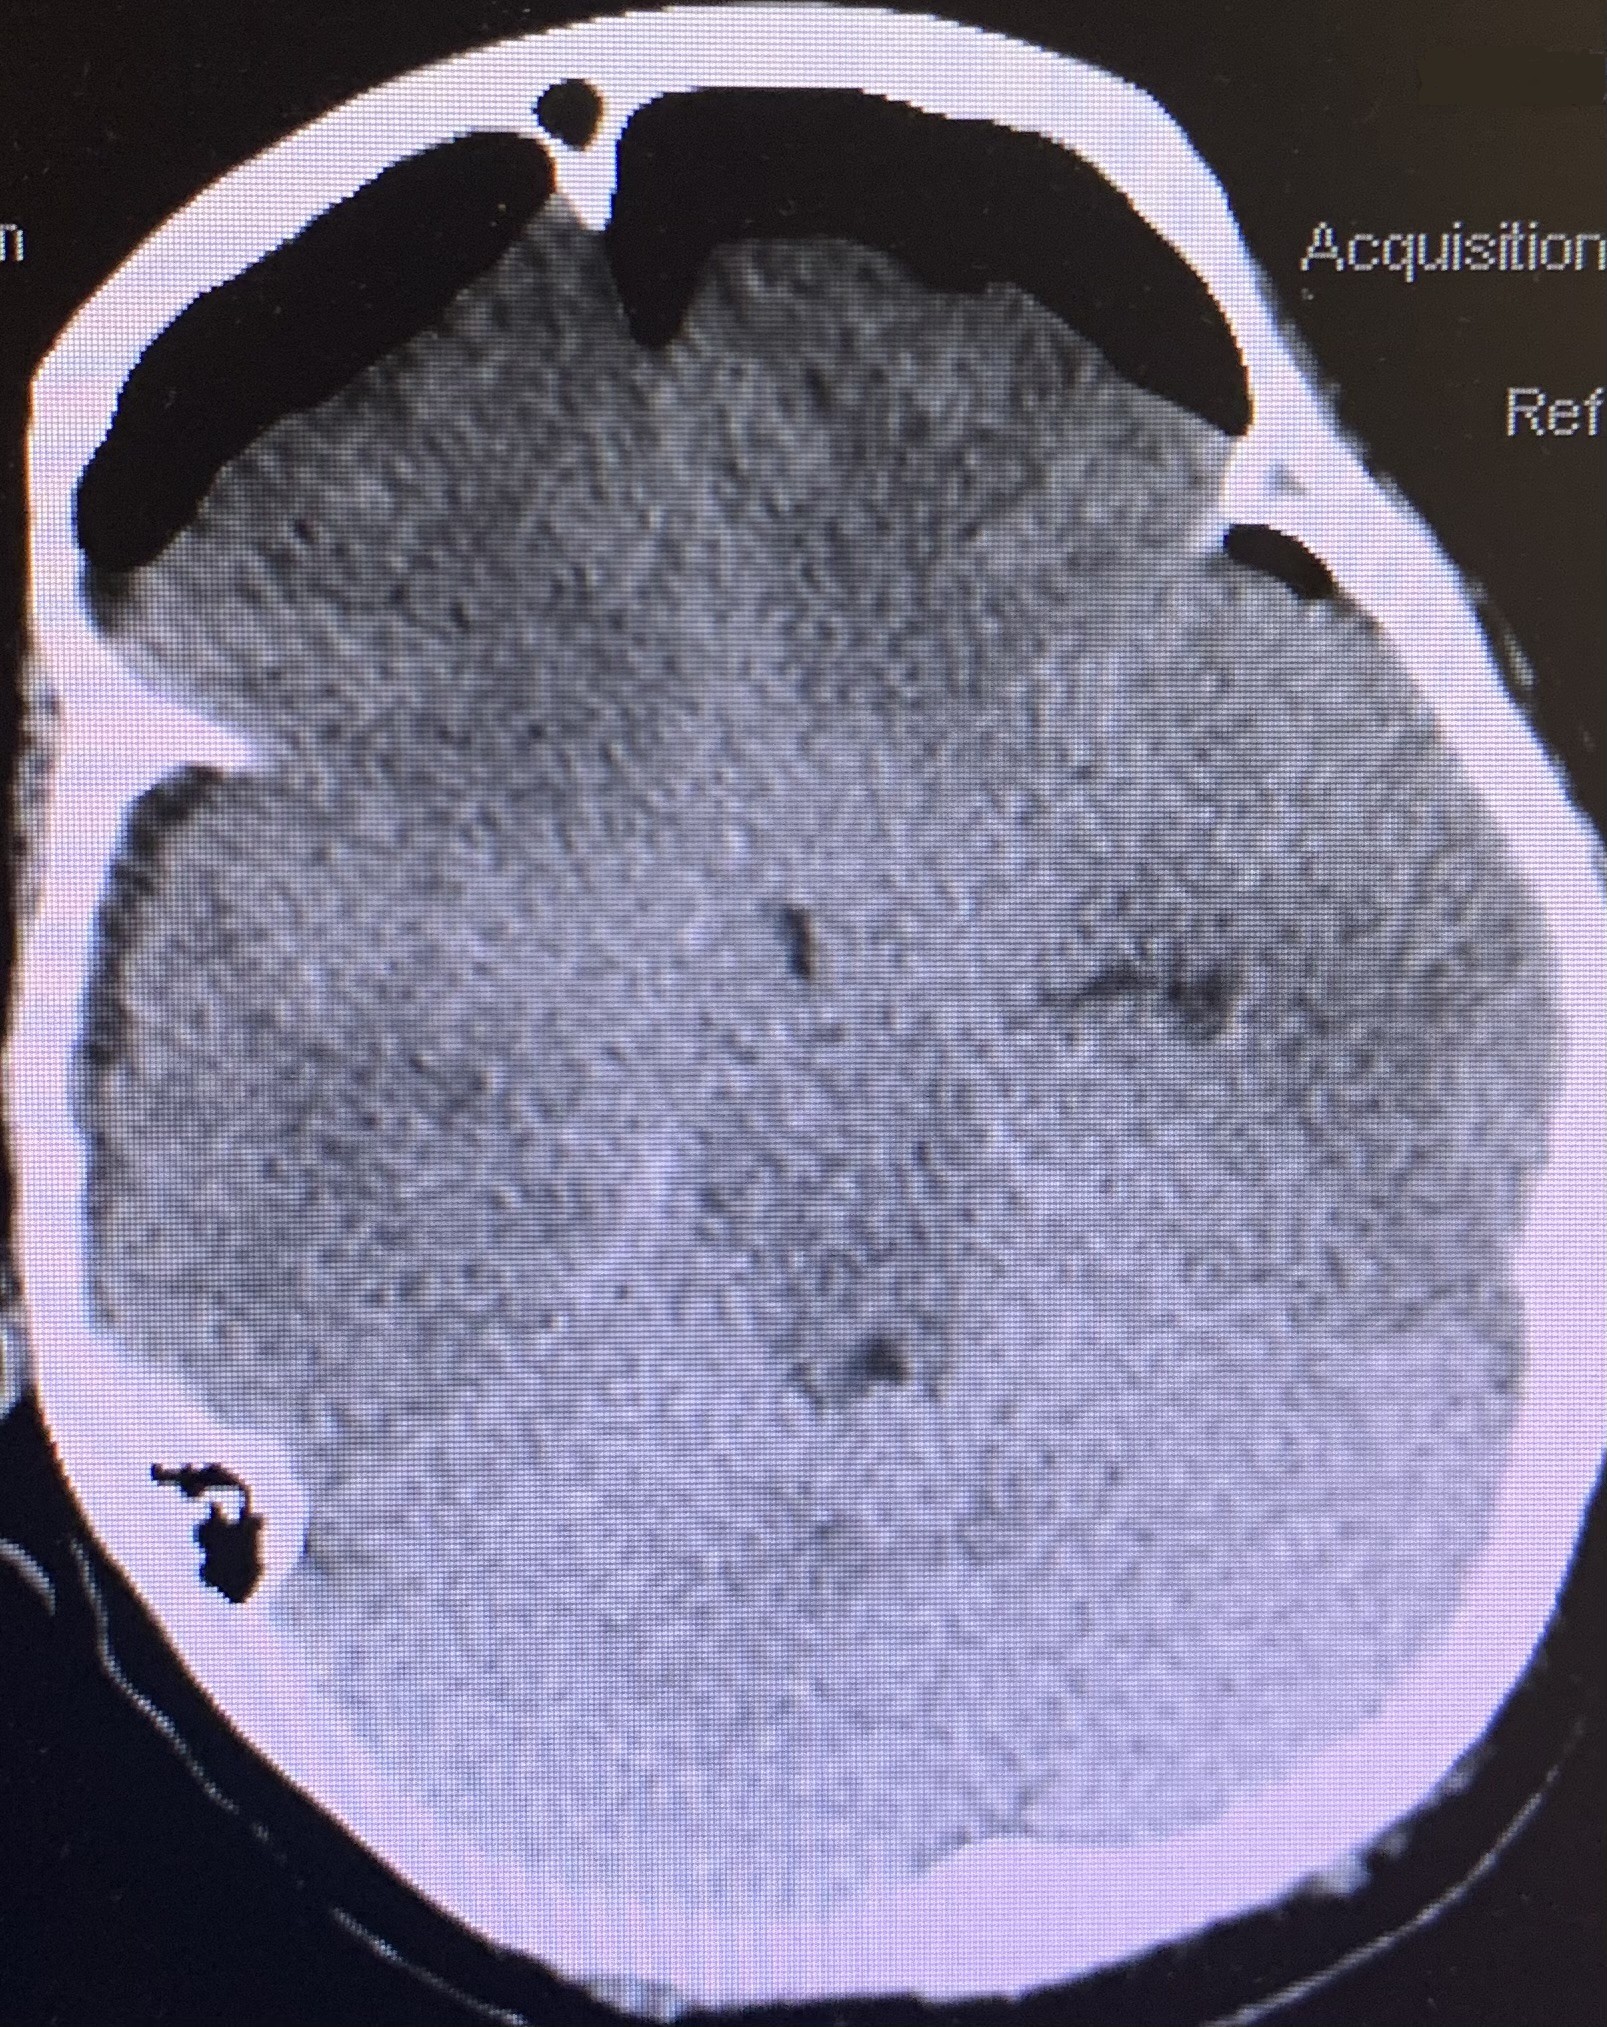

Patient was started on antibiotics and platelet transfusion, given the history of daily baby ASA used. Right Burr Hole craniotomy was done for evacuation of Subdural hemorrhage. After surgery, post op CTH demonstrated expected post op change with improved midline shift decreased to 4.2 mm. The patient was awake, alert and oriented after surgery, still had slight left facial droop, with improved left drift and left sided weakness (Figure 2).

Figure 2. CTH post op- expected pneumocephalus small SD fluid collection decreased midline shift to 4.2 mm